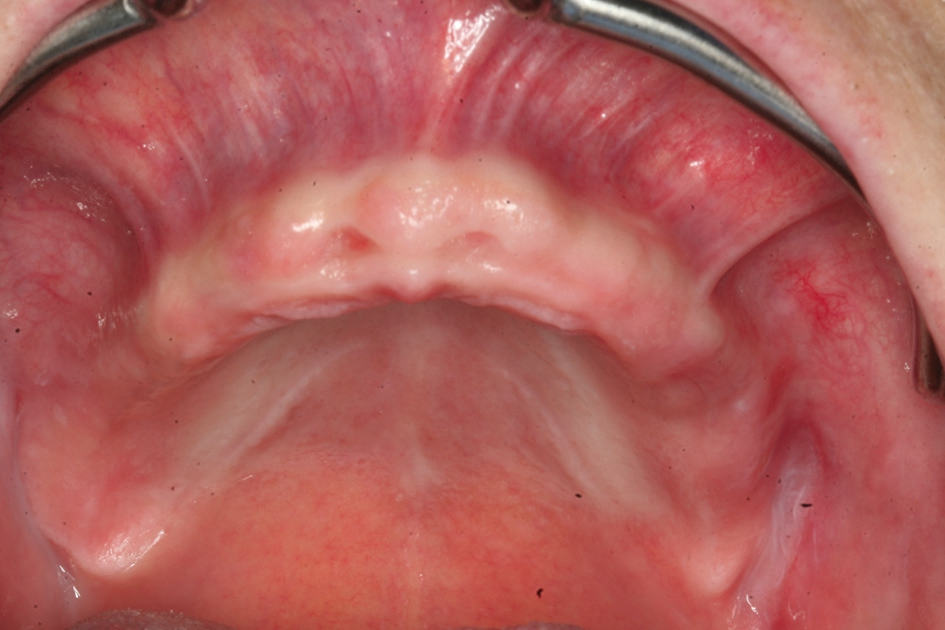

Das Bone Splitting, besonders im Oberkiefer, wird seit vielen Jahren propagiert [13]. Da unterschiedliche Vorgehensweisen vorgeschlagen werden, sind diese in Abhängigkeit des Knochenangebotes, der Anzahl der zu ersetzenden Zähne und der angestrebten prothetischen Versorgung auszuwählen [9, 18] (Abb. 1 und 2).

Die Diskussion erstreckt sich dabei sehr häufig, ob das vestibuläre Knochenangebot deperiostiert oder ob das Bone Splitting im Sinne eines gefäßgestielten Transplantates operiert werden soll [12]. Beim stärker atrophierten Kieferkamm zeigt sich dann die Problematik bei der gefäßgestielten Vorgehensweise häufig darin, dass durch das weite Aufdehnen des Kieferkamms krestal eine relativ breite Fläche entstehen kann, die durch die Auflagerung des Weichgewebes auf dem mobilisierten Kieferanteil nicht zu einem spannungsfreien Wundverschluss führen kann oder bei der Präparation eines Mukosalappens der gedehnte Bereich nicht mit Periost abdeckt wird. Ferner stellt sich die Problematik, dass bei einem zirkulären Vorgehen die Ernährung des Mukosalappens reduziert ist und es somit zu Wundheilungsstörungen kommen kann. Daher empfiehlt sich bei einem ausgedehnten Bone Splitting die Vorgehensweise mit der Präparation eines Mukoperiostlappens, da hier nach einer Periostschlitzung das Weichgewebe ausreichend mobilisiert werden kann, damit eine knöcherne Einheilung unter der geschlossenen Weichgewebsdecke erfolgt.